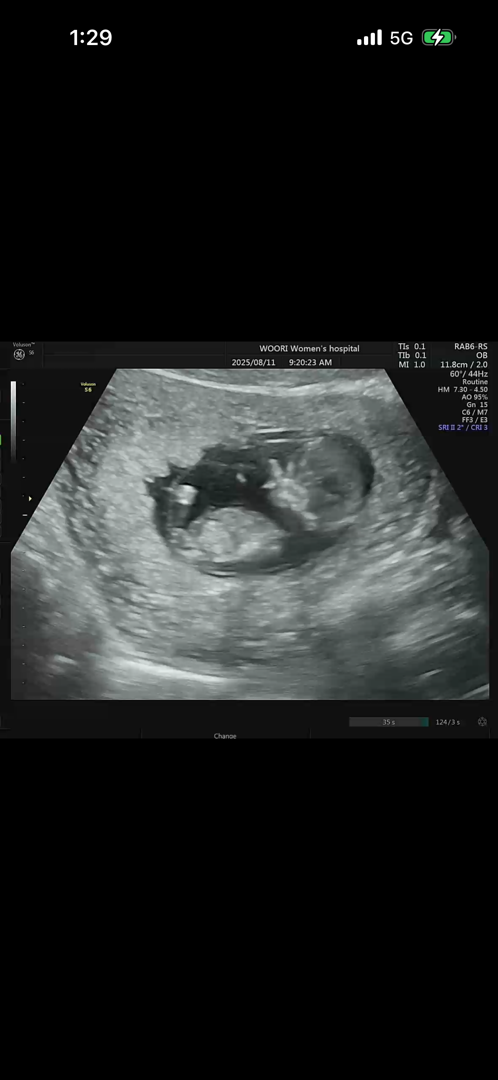

12주 각도법이요!!!

아들같나요 딸같나요?!